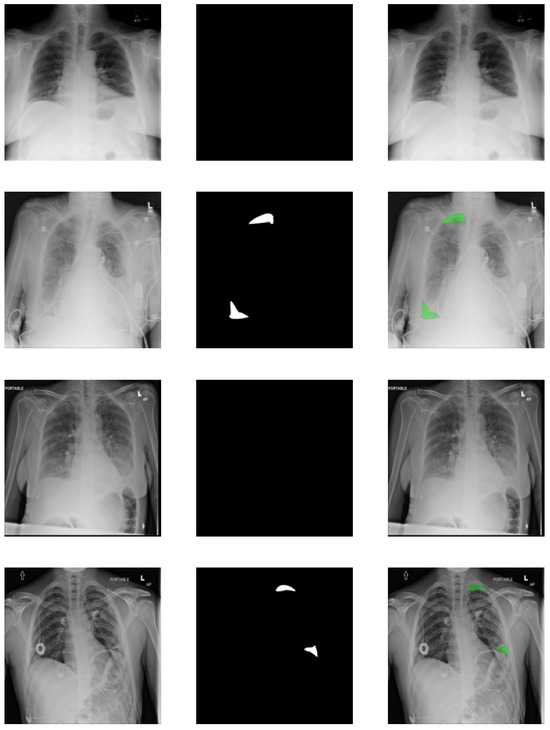

To show that our method works in general, a completely different dataset was selected: SIIM-ACR Pneumothorax containing chest X-rays. This dataset was created for a Kaggle challenge by taking the ChestX-ray14 dataset released by the National Institutes of Health (NIH) [50] and creating pixel-level annotation segmentation masks for images with positive pneumothorax (collapsed lung). The pixel-level annotations were created by the experts specifically for the challenge. Some of the examples can be seen in Figure 5. The final dataset consists of 9378 negative images and 2669 positive images. The size of the original images is 1024 × 1024 , but to simplify the models and speed up training, all were resized to 224 × 224 to be the same size as images from the first dataset so that the topologies could be identical.

As mentioned before, pixel-level annotations were created for all positive classes. The pixels of the regions containing the signs of pneumothorax are marked with the value 1 and everything else is marked as 0. These were then used as the segmentation masks in the reconstructions. For negative images, an empty array of zeros was used as the target, because there are no traces of pneumothorax anywhere.

In addition to the classification, C-CapsNet models generate reconstructions of the specified targets. Several examples of these can be seen in Figure 11. The first column shows the input images for all models, the second the output of the best-performing original image reconstruction model, the third column shows the segmentation masks of these images, and the final column shows the outputs of the best-performing segmentation reconstruction model. These four examples were chosen, as they best represent the usual cases on other data. The false negative images have no segmentation and the false positive have random regions highlighted.